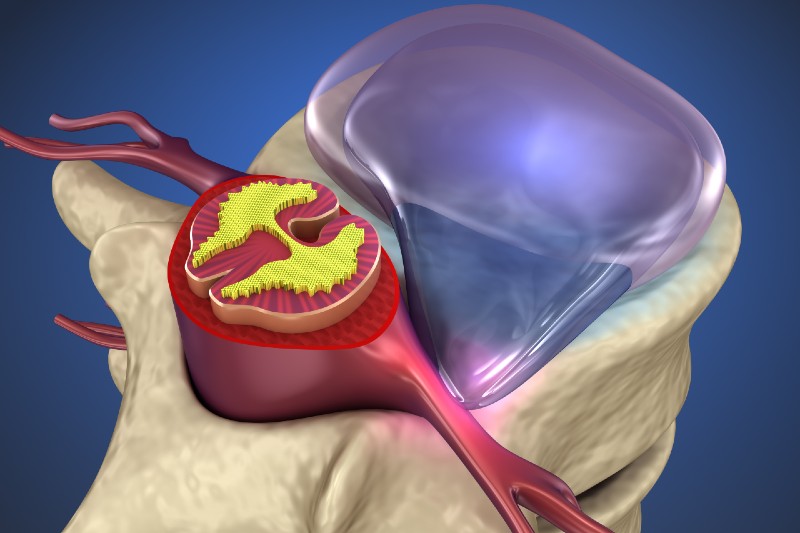

خلاصهای از فصل «بیماری دیسک کمری» از کتاب Youmans and Winn Neurological Surgery 1. پاتوفیزیولوژی و اپیدمیولوژی با افزایش سن، دیسکهای بینمهرهای دچار دژنراسیون میشوند که میتواند منجر به کاهش ارتفاع دیسک، فتق دیسک و تنگی کانال نخاعی شود. عوامل خطر شامل سن بالا، فعالیتهای فیزیکی سنگین، سیگار کشیدن و ژنتیک هستند. 2. […]

ترمیم دیسک پاره شده آیا دیسک پاره شده ترمیم میشه؟ پارگی دیسک بینمهرهای بسته به شدت آسیب و شرایط بیمار ممکن است به درجاتی ترمیم شود یا کنترل گردد، اما بهبودی کامل به شکل ترمیم بافتی مانند قبل معمولاً رخ نمیدهد. با این حال، بسیاری از افراد با درمانهای طب فیزیکی و توانبخشی بدون نیاز […]